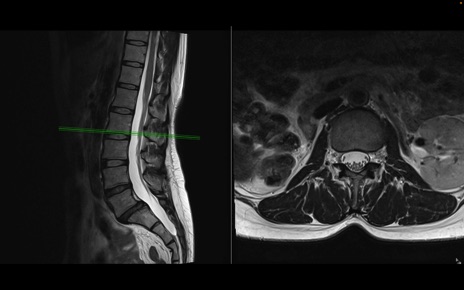

腰椎MRI

T2WI(横断像)

T2WI(矢状断像)